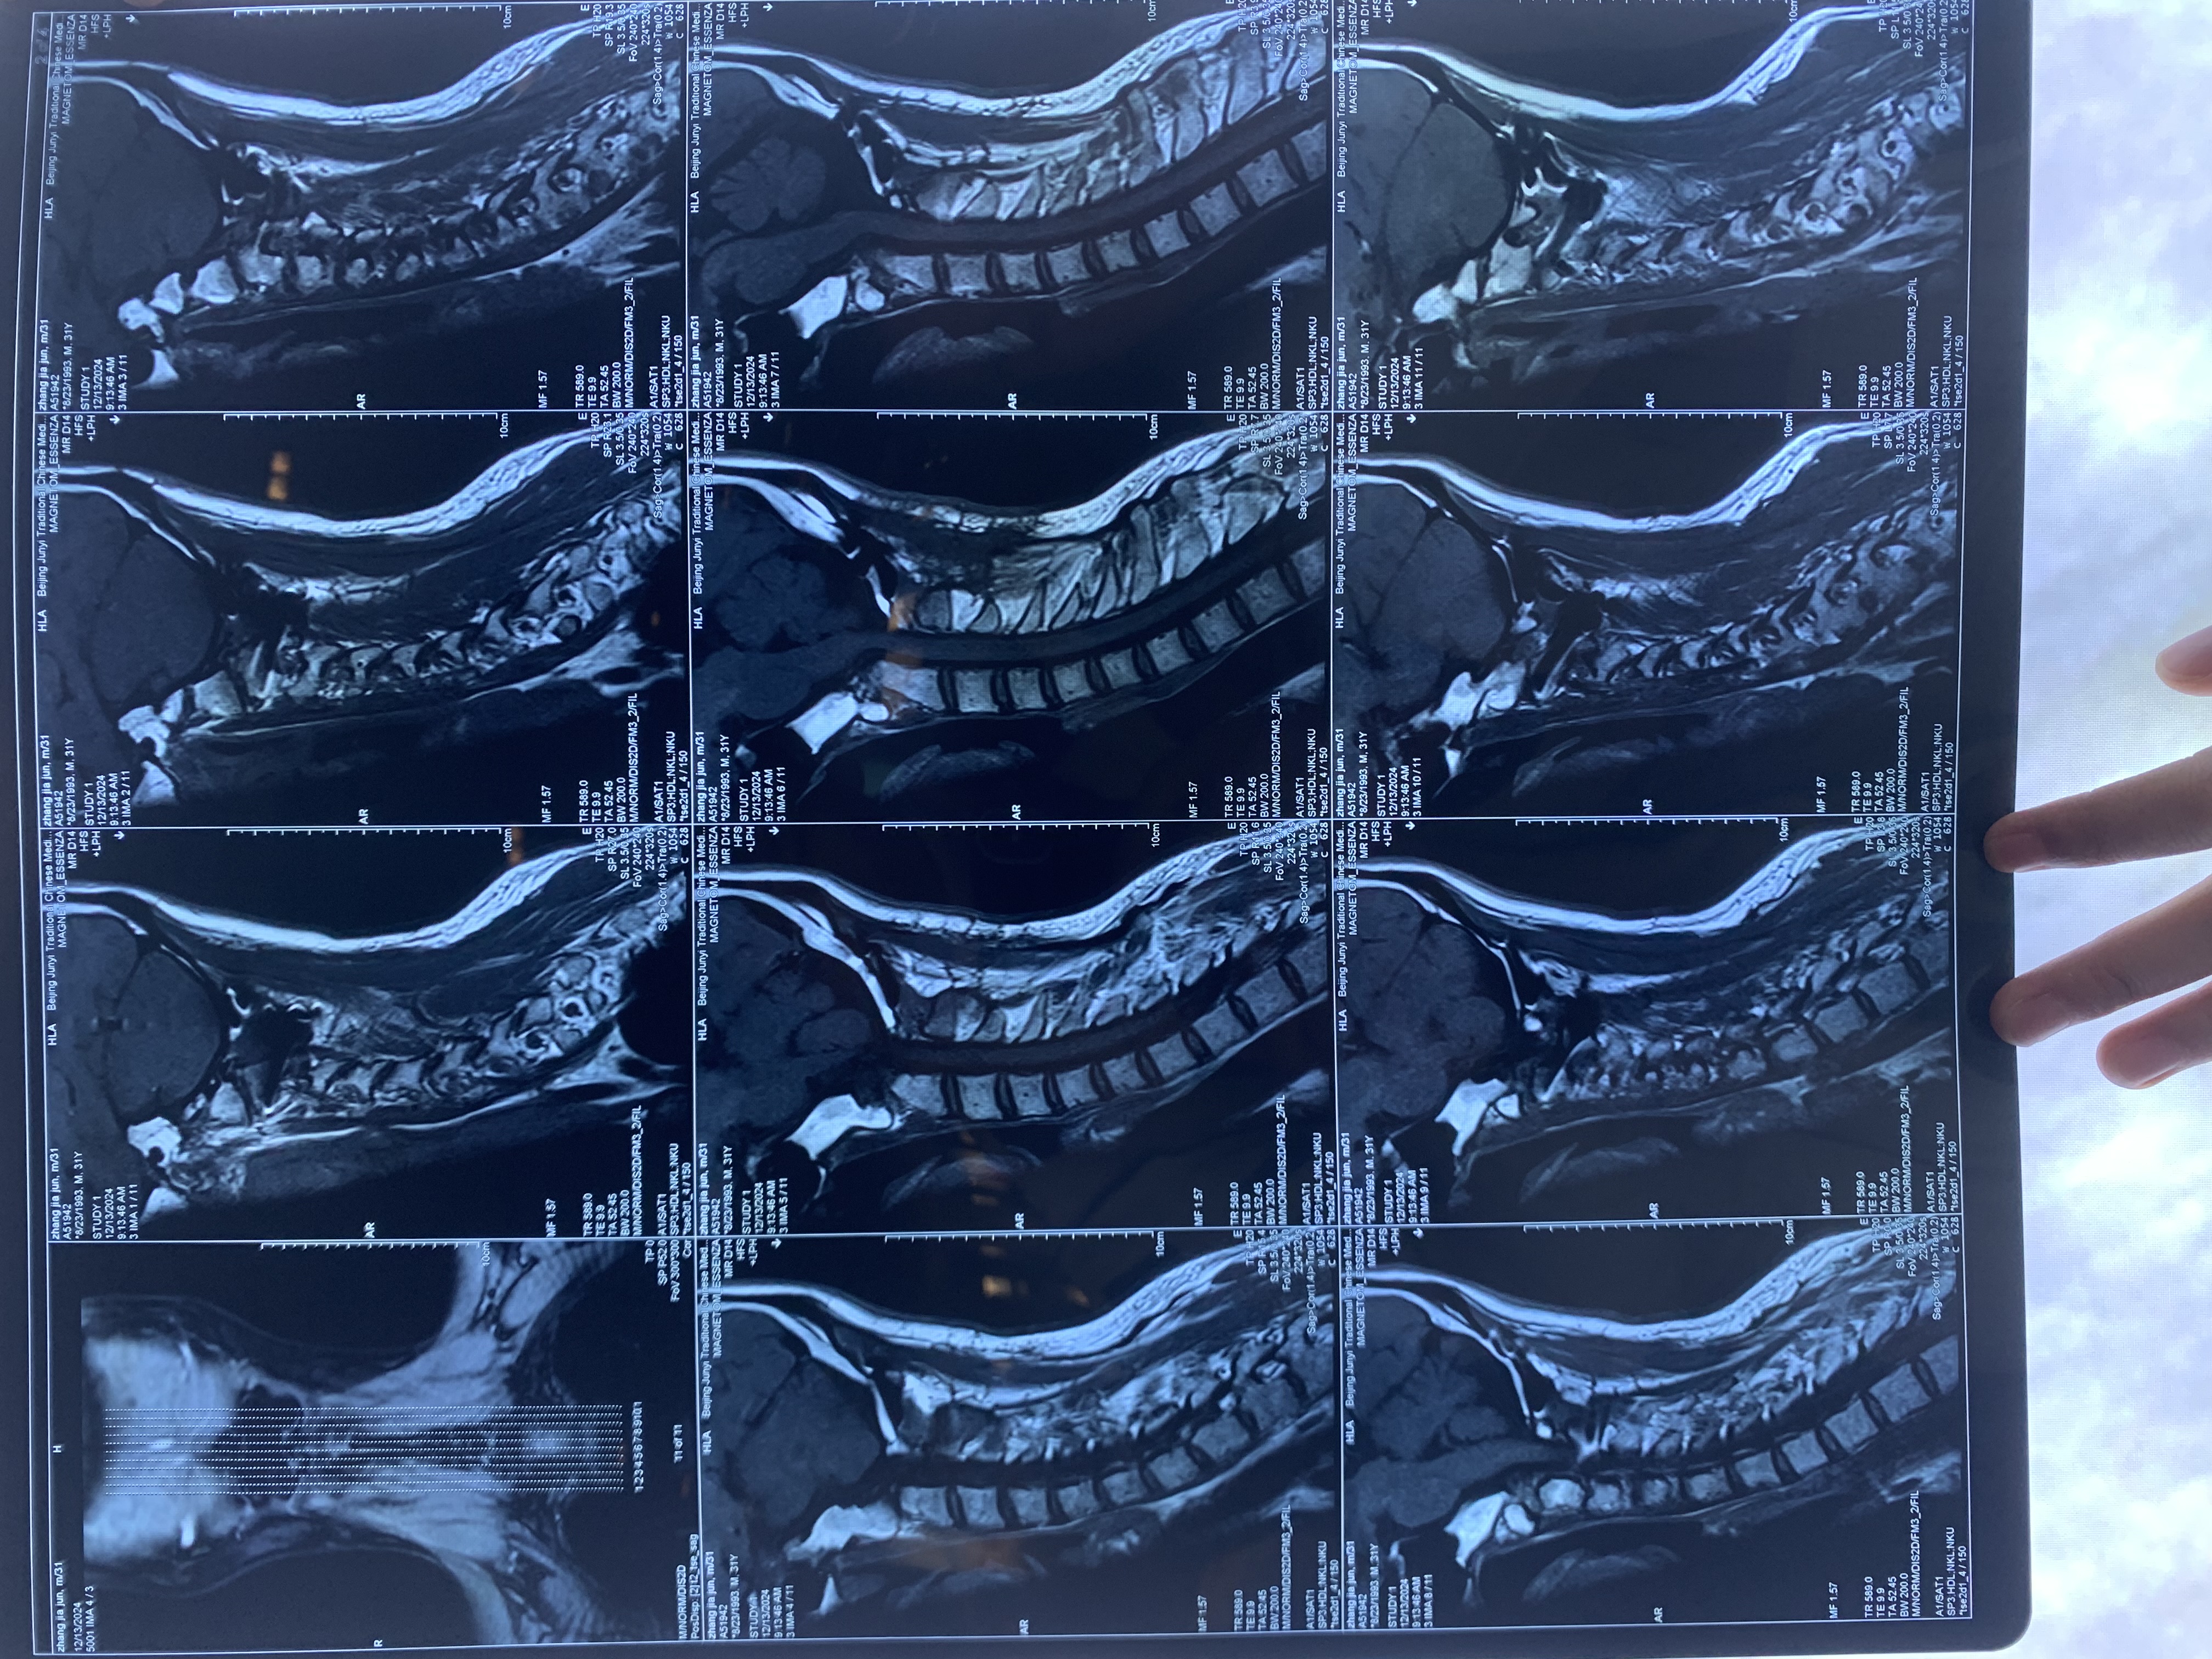

• 术后状况:头晕症状还在,但握拳有劲了,第二天看ct片子,寰齿间隙还是大于3mm,颅底凹陷没有任何改善。

• 术后影像:

• 2024.12.13,去北京拍片,当天走路有点多,感觉脑袋里面疼。影像报告脱位和颅底凹陷都还在,影像如下: